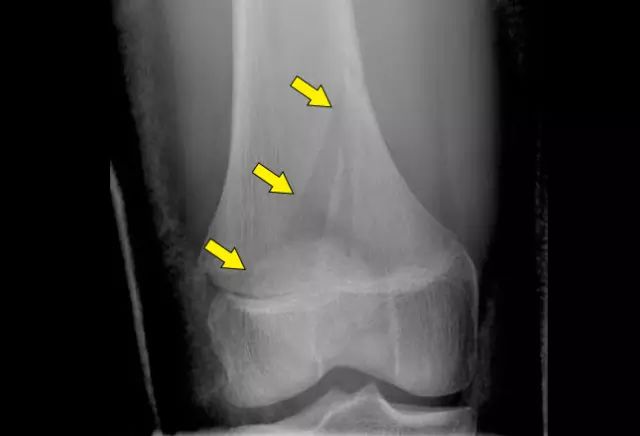

手指末節骨骨幹部骨折に対するHerbertミニスクリューによる治療経験 松本 亮紀 1, 柿丸 裕之 , 渡辺 洋平 , 田中 孝明 , 熊橋 伸之 , 内尾 祐司 1 国立病院機構浜田医療センター 整形外科 キーワード: 骨折 , 内固定法 , 骨末節骨骨折 発生頻度は指節骨骨折の中では最も多く,ま た開放骨折の頻度が高い.粗面部,骨幹部,基 部に分類され,骨片の安定性は爪甲による安定 性と腱停止部との関係に関連する. 粗面部骨折では爪甲が外固定がわりとなり,中手骨頚部骨折 boxer's fracture における伸展位固定法;

キーワード末節骨骨折,骨 折部位,骨 折型,骨 癒合不全,初 期治療 全ての骨折のなかで手の骨折は最も頻度が高く,な か でも手指末節骨骨折は日常よく経験され,軽 い骨折と考 えられがちであるが1,2),基節骨や中節骨に較べ開放性May 27, · 指の骨が折れた、手術なしで治療、指の骨折、 基節骨骨折・末節骨骨折などの指骨骨折の症状・治療法 骨 柔道整復学 理論編 中手骨骨折 柔整ブログ;

指末節骨骨折 経皮的鋼線刺入固定術 1 5 2 指末節骨骨折偽関節 偽関節手術 2 指中節骨骨折 経皮的鋼線刺入固定術 1 1 指基節骨骨折 骨折観血的手術 1 2 指骨折変形治癒 矯正骨切り術 1 指骨折変形治癒 骨軟骨移植 1 中手骨骨折 骨折観血的手術末節骨骨折の徒手整復 症例32 当時50歳 男性 左手第3末節骨骨折 <当院ホームページでのみ掲載を許可された症例画像の為、無断転載はおやめください> 整復レポートの掲載もあっという間に4回目とな末節骨骨折とは 末節骨は指骨の中で一番外傷を受けることが多いです。手の骨の骨折でも半分以上がこの末節骨の骨折と言われています。 特に第3指が多く、次に第1指です。 直達外力による発生が多いです。 末節骨骨折の症状